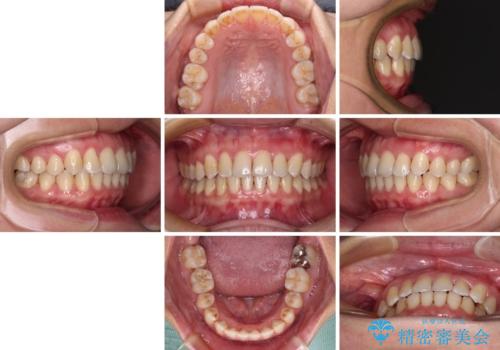

前歯の反対咬合 急速拡大装置とワイヤー装置であっという間の矯正治療

上顎の拡大に伴い反対咬合があっという間に改善されました。

元々の歯列不整は軽微であったため、僅か1年の期間で治療を終えることができました。